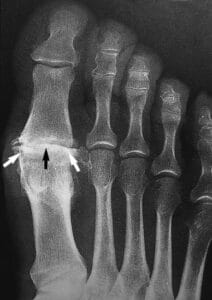

X-rays. X-rays provide detailed pictures of dense structures such as bone. An X-ray of an arthritic foot may show narrowing of the joint space between bones (an indication of cartilage loss), changes in the bone (such as fractures), or the formation of bone spurs. Weightbearing X-rays are taken while you stand. They are the most valuable additional test in diagnosing the severity of arthritis and noting any joint deformity associated with it. In arthritic conditions, if X-rays are taken without standing, it is difficult to assess how much arthritis is present, where it is located in the joint, and how much deformity is present. So, it is very important that, when possible, X-rays are taken standing

This X-ray reveals osteoarthritis in the metatarsophalangeal joint of the big toe. Joint space narrowing (black arrow) and bone spurs (white arrows) can be seen.

Reproduced from Johnson TR, Steinbach LS (eds): Essentials of Musculoskeletal Imaging. Rosemont, IL. American Academy of Orthopaedic Surgeons, 2004, p. 631.